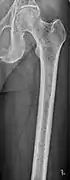

Bone pain

Illustration showing the most common site of bone lesions in vertebrae

Bone pain affects almost 70% of people with multiple myeloma and is one of the most common symptoms.[2]:653[22] Myeloma bone pain usually involves the spine and ribs, and worsens with activity. Persistent, localized pain may indicate a pathological bone fracture. Involvement of the vertebrae may lead to spinal cord compression or kyphosis. Myeloma bone disease is due to the overexpression of receptor activator for nuclear factor κ B ligand (RANKL) by bone marrow stroma. RANKL activates osteoclasts, which resorb bone. The resultant bone lesions are lytic (cause breakdown) in nature, and are best seen in plain radiographs, which may show "punched-out" resorptive lesions (including the "raindrop" appearance of the skull on radiography). The breakdown of bone also leads to the release of calcium ions into the blood, leading to hypercalcemia and its associated symptoms.[23]